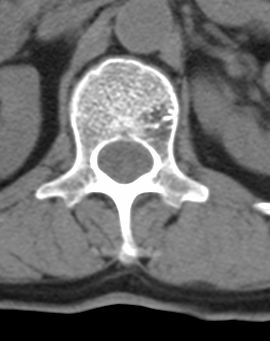

标题: CT22439:腰椎低密度病灶(腰椎血管瘤) [打印本页]

标题: CT22439:腰椎低密度病灶(腰椎血管瘤)

患者 女 54岁 外伤后检查发现l1椎体局部密度减低,请问这是什么病灶?

考虑腰椎血管瘤

椎体内部局限性骨小梁稀疏、粗大改变,周围未见软组织肿块,首先考虑椎体血管瘤。

l1椎体血管瘤可能性大;建议必要时行mri检查。